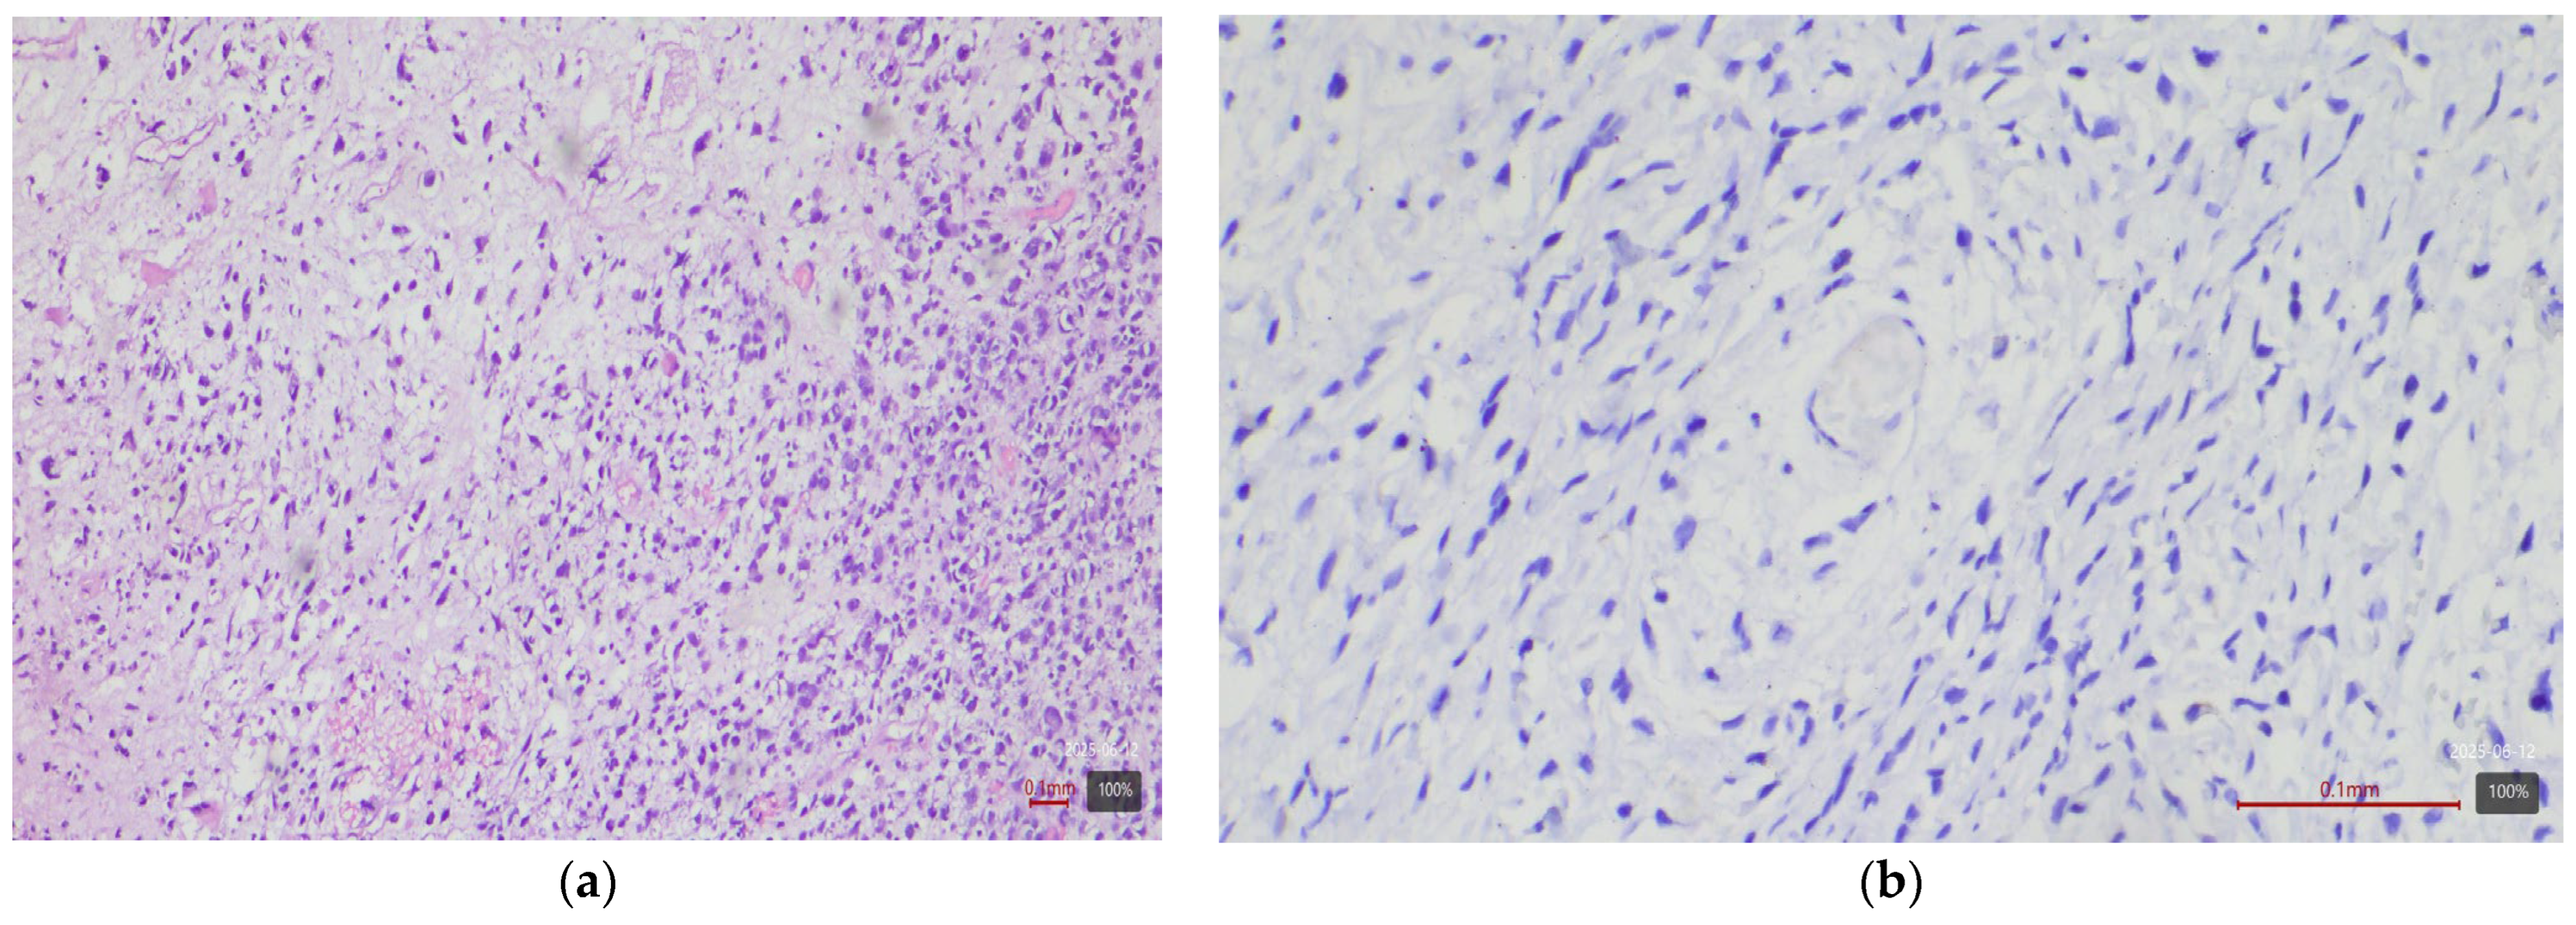

2.3. Histological and Molecular Subtyping of Tumors

2.4. Immunohistochemical Study of HER2

2.5. Interpretation of HER2 Status